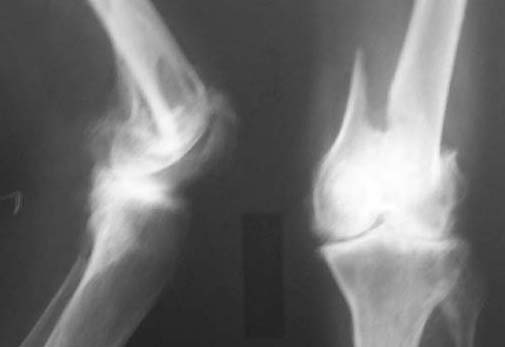

68 year old gentleman injured in a road traffic accident. Sustained closed fracture left supracondylar region with intercondylar extension. Found to have bilateral chronic lymphaedema of legs with eczema. History of recurrent frequent breakdown. Has been a chronic smoker though stopped for 2years (smoked for almost 55 years of his life). Distal pulses not felt due to thickened skin but detected on doppler probe.Both knees show marked osteoarthritic changes. Patient ambulant till injury. Clinical picture and X-rayattached.

From: Gregory J Schmeling

From what I can see, the knee is very arthritic, and his skin is poor below the tibial tubercle as you stated. The skin around the knee looks fine. I would favor retrograde femoral nailing. This could be done percutaneous, or with midline approach. If locked retrograde nailing is not available, I recommend rush rods. You don't necessarily need to fix the condyles. This could be done percutaneously, and likely will get him out of bed. I favor traction over Iliazorov. I find the dangers of traction tend to be underlying medical problems, and poor nursing care rather than the traction itself.